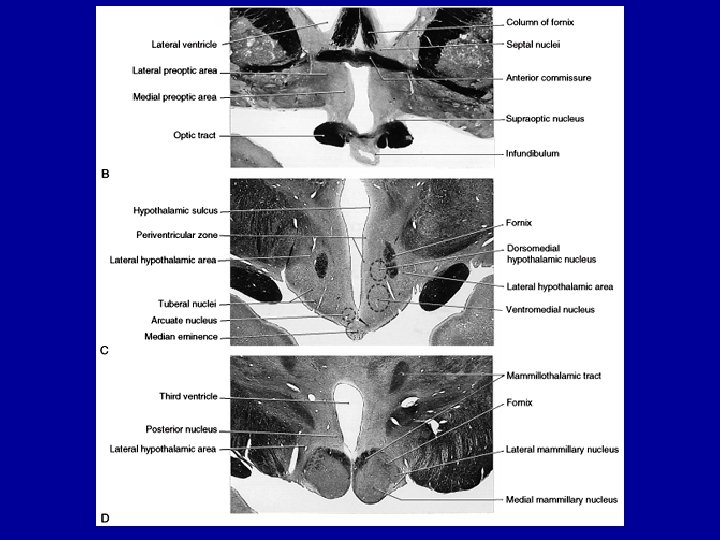

Anatomy of Hypothalamus • Figure 29 -4, textbook • Anterior posterior: 4 regions – preoptic area – supraoptic region – tuberal region

Preoptic area • Medial preoptic: LHRH • Lateral preoptic: motor control

Supraoptic region • Paraventricular: oxytocin and vasopressin (ADH) • Anterior: heat dissipation • Supraoptic: oxytocin and vasopressin Paraventricular: oxytocin and vasopressin (ADH) Anterior: heat dissipation • Suprachiasmatic: circadian rhythms Supraoptic: oxytocin and vasopressin (ADH) Suprachiasmatic: circadian rhythms

Tuberal region Dorsomedial: “sham rage” Ventromedial: satiety center Arcuate: releasing hormones and inhibiting hormones

Mammillary region • Posterior nucleus: heat conservation • Mammillary nucleus: learning and memory Posterior nucleus: heat conservation Mammillary nucleus: learning and memory